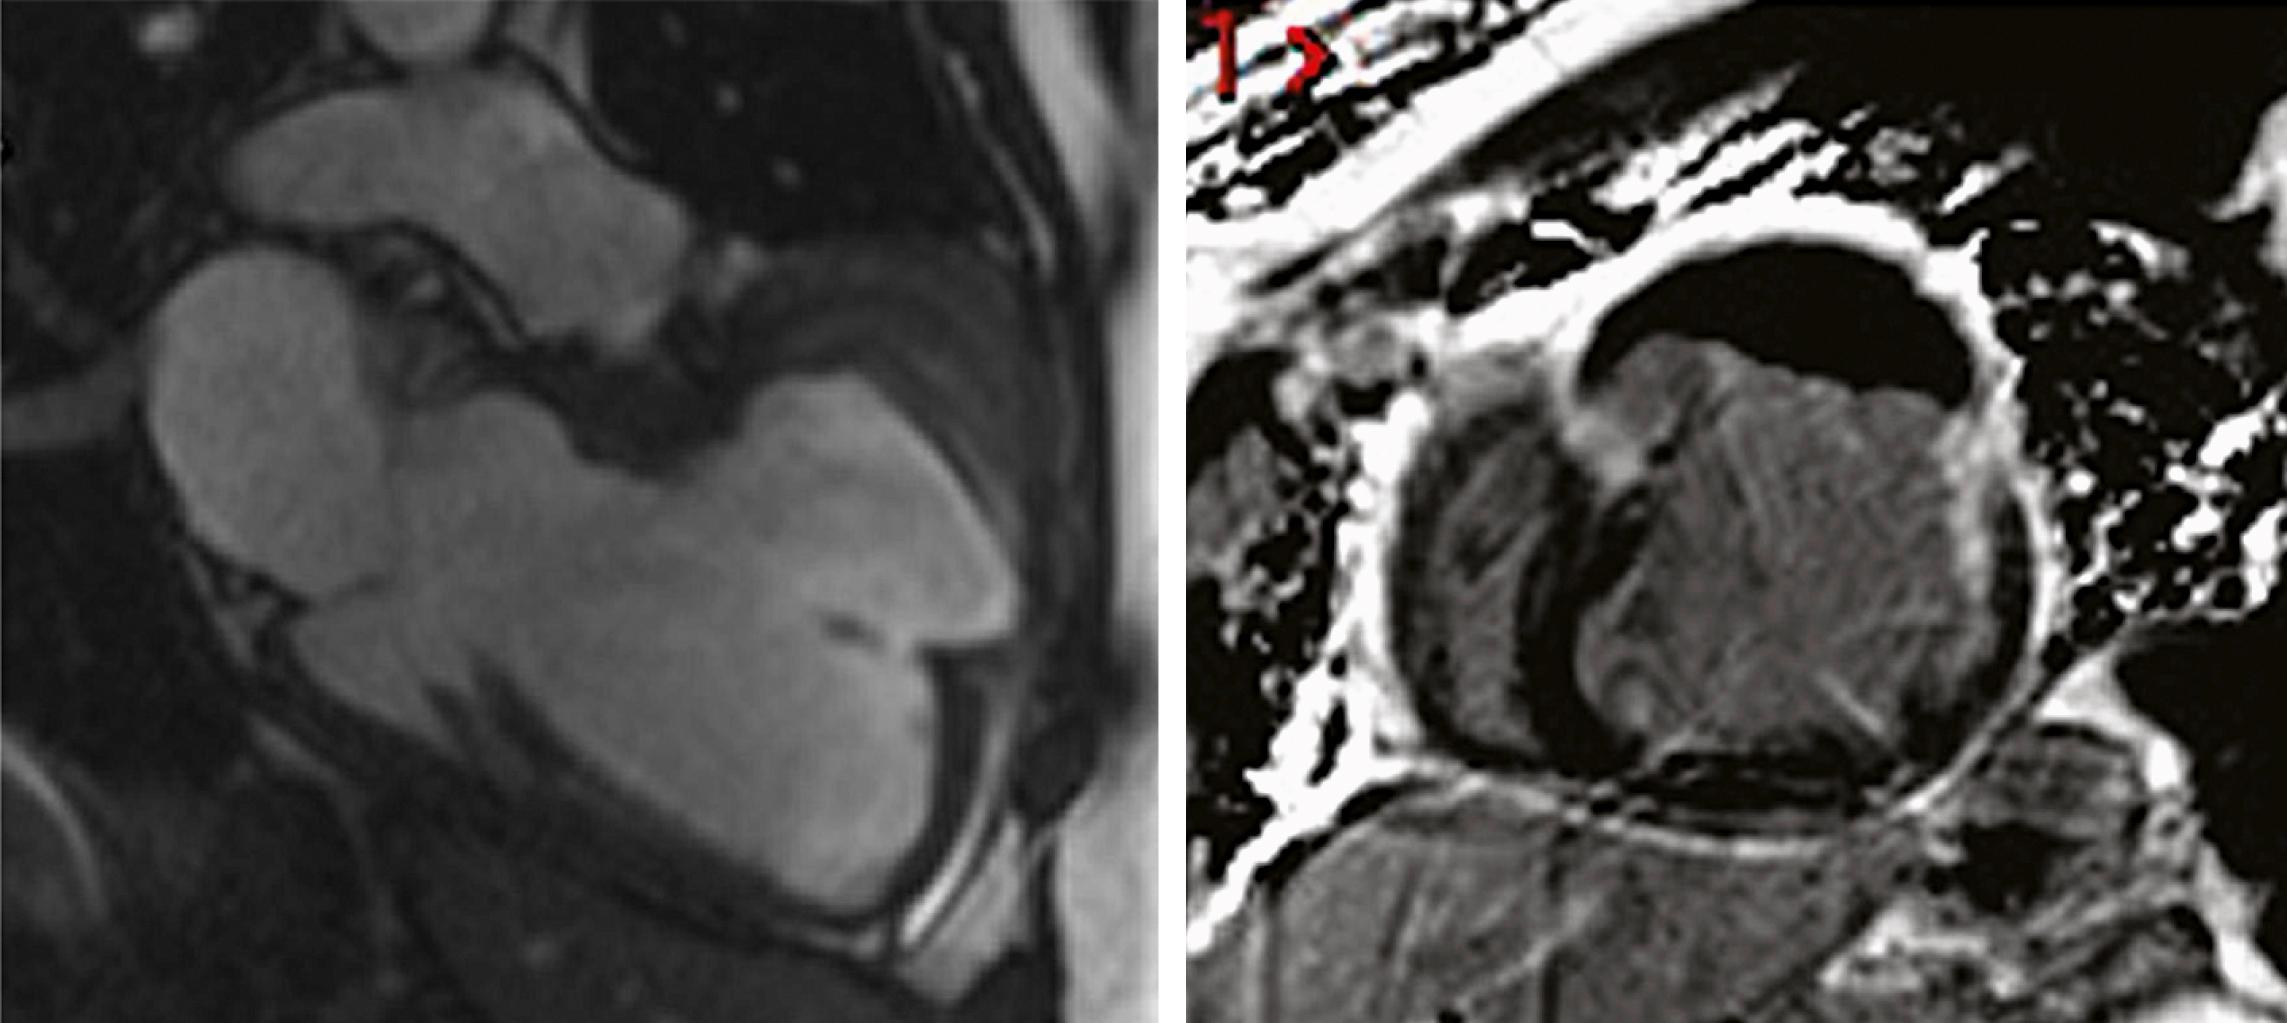

FIGURE 19.5, Microvascular obstruction. Left, Short-axis T2∗-weighted image from a porcine model of reperfused MI demonstrating intramyocardial hemorrhage in the anteroseptum. Right, Short-axis phase-sensitive inversion recovery LGE image in the same animal demonstrating transmural LGE with a mid-wall region of intramyocardial hemorrhage.

FIGURE 19.6, Ventricular pseudoaneurysm. Left, A two-chamber long-axis SSFP cine image at end-diastole in a patient 5 years after anterior MI demonstrating a chronic anterior pseudoaneurysm. Note the narrowed neck of the pseudoaneurysm. Right, Short-axis phase-sensitive inversion recovery LGE image from the same patient demonstrating enhancement of the fibrous outer layer of the pseudoaneurysm, which is lined with thrombus, which appears black.